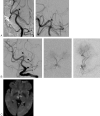

A patient with acute top of the basilar syndrome clinically was found to have only a small basilar artery filling defect but complete occlusion of the artery of Percheron. Intra-arterial thrombolysis resulted in favorable neurologic outcome. To our knowledge, this is the only case of angiographically proved and treated artery of Percheron occlusion. The value of this report is that reperfusion of ischemic areas was only achieved when persistent investigation disclosed artery of Percheron occlusion.